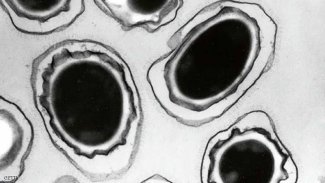

"البكتيريا الخارقة" تنذر العلماء.. وأمراض مستعصية على الطريق "البكتيريا الخارقة" تنذر العلماء